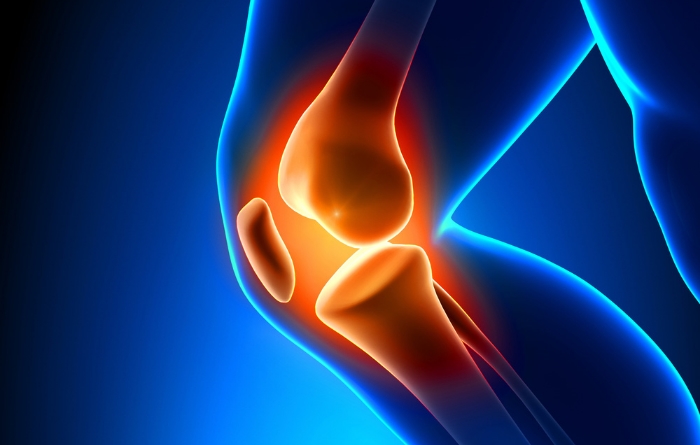

Joint Replacement

Because like all surgeries, joint replacement procedures do require some recovery time, they are normally only considered after all other non-surgical options have been discussed and/or attempted. Normally, joint surgery provides significant and wonderful results for the majority of patients. At Rothman Orthopaedic Institute, patients have the advantage of being seen by physicians who have actually helped develop and launch joint replacement techniques and who are considered to be well-renowned authorities on the topic of joint replacement

If you experience pain in any of your joints due to physical activities such as walking, running, and climbing stairs, it may be time to have a Rothman Orthopaedic Institute specialists diagnose your case. Joint replacement may be the answer for you. When simply sitting in a favorite chair or sleeping in your bed causes enough pain to wake you or make your life extremely uncomfortable, joint replacement may be able to get you back to an active lifestyle with less pain.